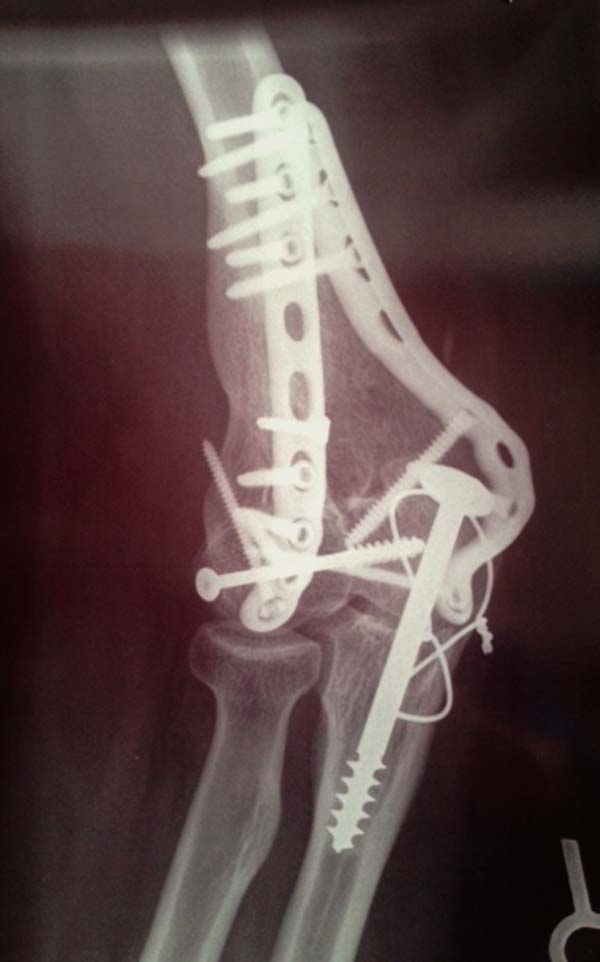

Из представленнего материала видно, что между снимками нет разницы.

Отсутствует репозиция не только медиального, а также латерального

мыщелка. На боковом снимке мыщелок расположен спереди, а прямом головка

луча упирается в край мыщелка, что означает ротацию. Отсутствует

компрессия между мыщелками, а один шуруп не смог удержать медиальную

сторону, которая при первом же движении рассыпалось.

Примеры: первому более 15 лет фиксирован шурупом и tension band

technique, а второй перелом открытый больной 80 лет, после наружного

фиксатора в первом этапе и окончательная фиксация вторично. Третьий раз

внесуставная остеотомия...